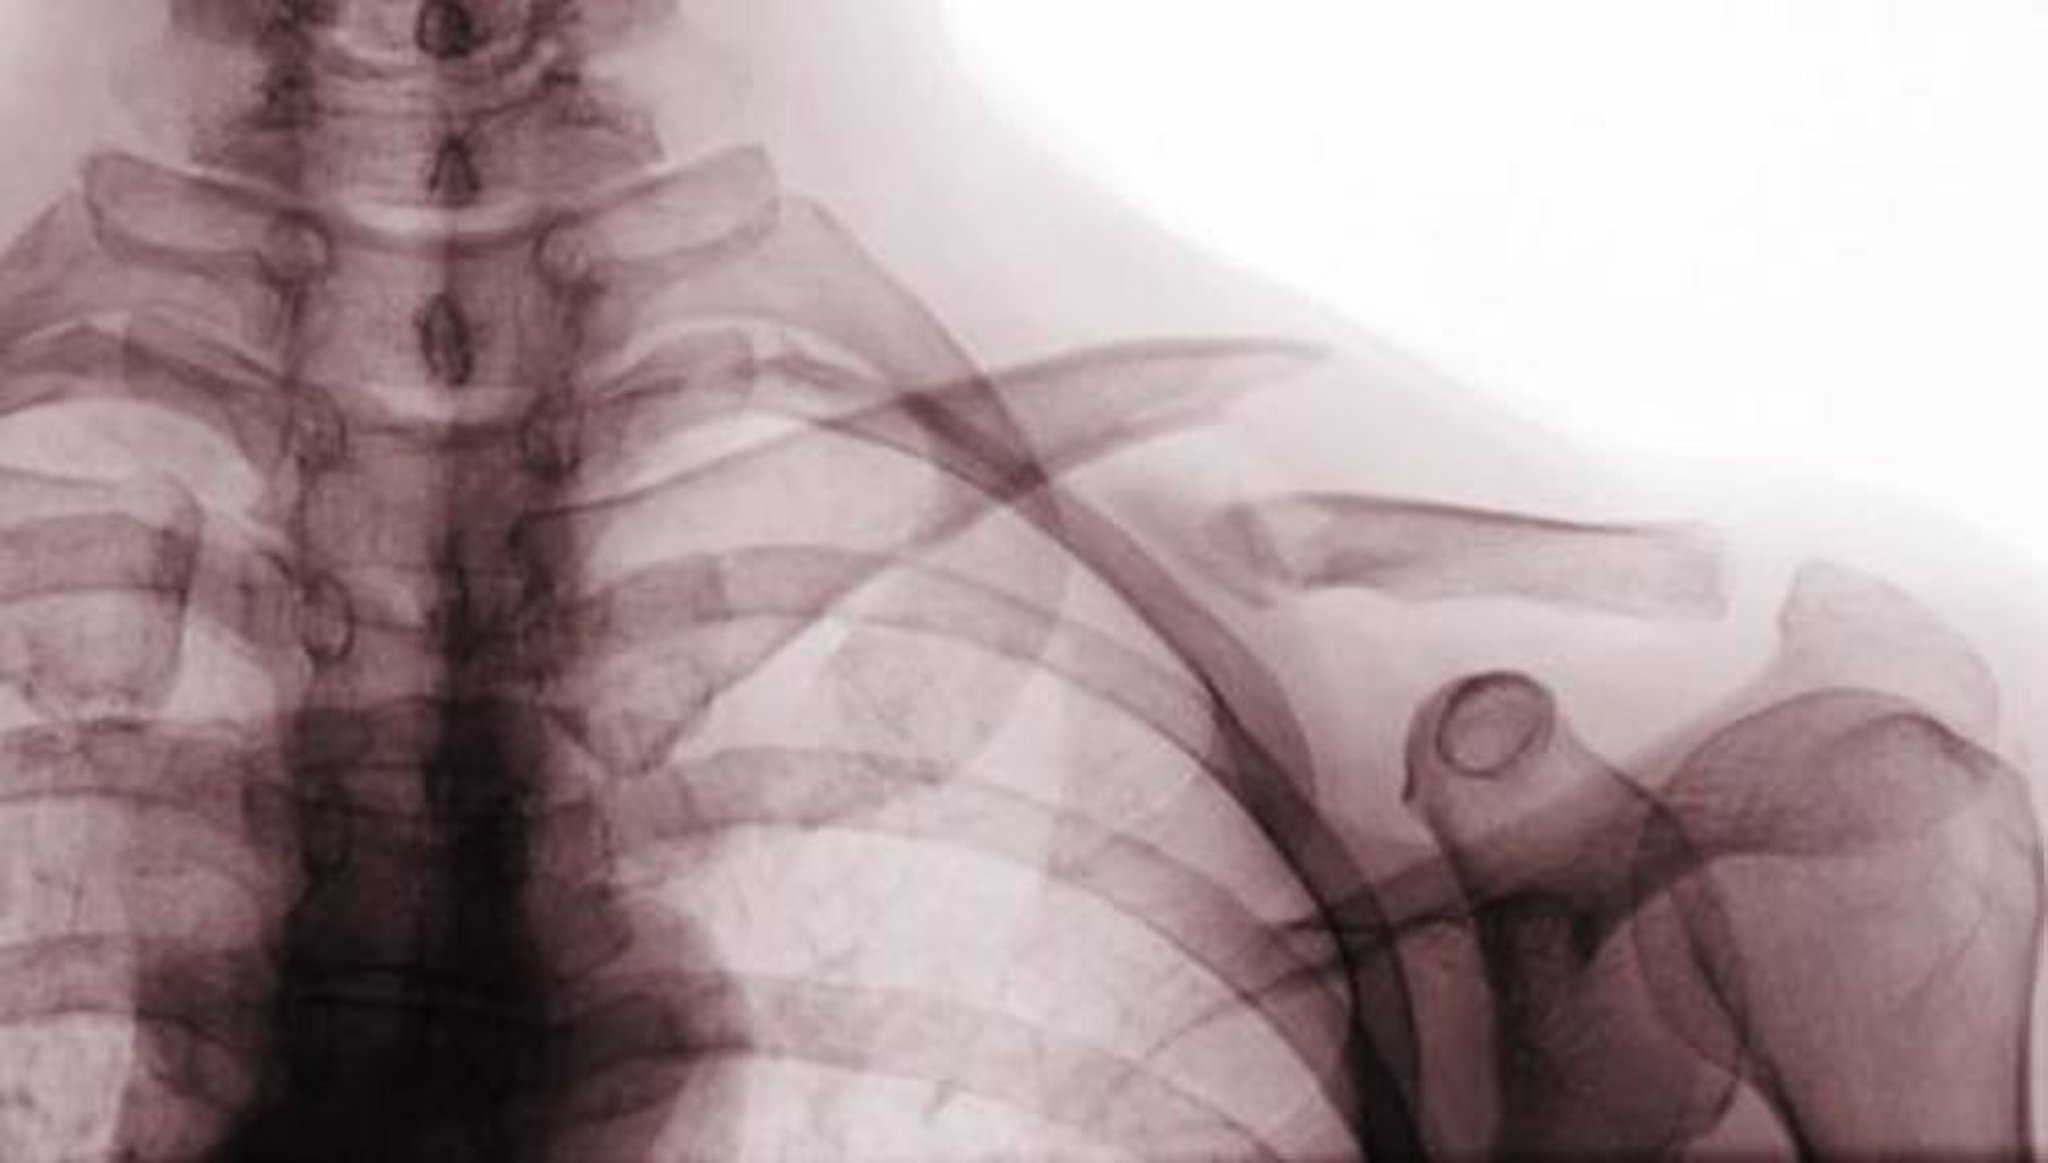

Hình chụp X-quang trước sau này cho thấy gãy di lệch của 1/3 giữa của xương đòn (gãy xương loại A).